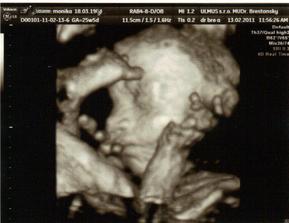

✿♥♥♥♥Bude to dievčatko!!!!! ♥♥♥♥✿

Bude to Stella 🙂

krasne 3D sono 🙂